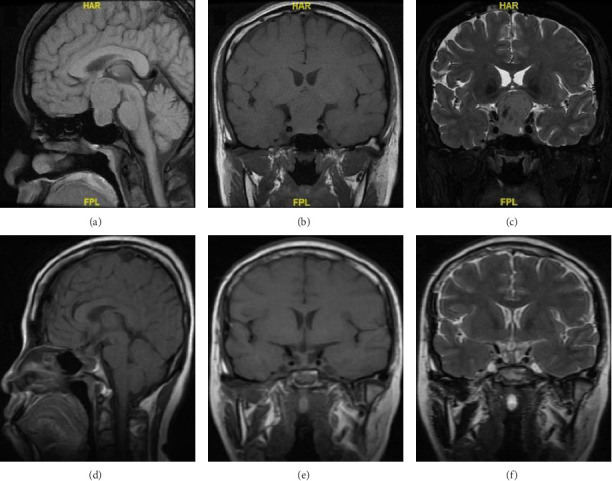

背景:妊娠期垂体神经内分泌肿瘤(pitNETs)的治疗具有挑战性。多学科团队(MDT)的参与有利于协同决策。然而,这方面还没有得到很好的记录。我们提供了妊娠期pitNETs的病例,并总结了我们在mdt指导下的治疗经验。方法:我们进行了一项回顾性研究,纳入了1995年3月至2024年7月期间在我们研究所治疗的所有妊娠pitNETs患者。结果:索引期间,121例pitNETs患者在妊娠期间来我院就诊,其中111例接受保守治疗,10例因进行性视力缺损等症状行手术治疗。纳入手术病例的年龄为33岁,手术时的妊娠期为13至36周(妊娠早期1周,妊娠中期4周,妊娠晚期5周)。在切除的肿瘤中,6例无功能,另外4例有功能(1例乳营养型,1例生长营养型,1例甲状腺功能)。所有手术病例均在神经外科、内分泌科、眼科、产科、儿科和麻醉科医生的指导下接受mdt治疗,所有患者的肿瘤全部切除,视力改善,分娩成功。结论:MDT指导下的妊娠期pitNETs治疗是必要的。对于症状迅速恶化的患者,手术切除肿瘤是必要的。全身麻醉下经蝶窦手术对妊娠期pitNETs患者是安全的。

Background: Management of pituitary neuroendocrine tumors (pitNETs) during pregnancy is challenging. Involvement of the multidisciplinary team (MDT) may benefit the collaborative decision-making. However, this aspect has not been well documented. We provided cases with pitNETs during pregnancy and summarized our experience on the MDT-guided management. Methods: We performed a retrospective study enrolling all pregnant patients with pitNETs treated at our institute between March 1995 and July 2024. Results: During the indexed period, 121 patients with pitNETs consulted our institute during pregnancy, with 111 of them being treated conservatively and 10 undergoing surgery due to progressive visual defect and other symptoms. The age of the included surgical cases was 33 years, and the gestational session at surgery ranged from 13 to 36 weeks (1 in the first trimester, 4 in the second, and 5 in the third). Of the resected tumors, six were nonfunctioning and the other four were functioning (1 lactotroph, 1 somatotroph, and 1 thyrotroph). All surgical cases received MDT-guided management by physicians from neurosurgery, endocrinology, ophthalmology, obstetrics, pediatrics, and anesthesiology, leading to gross total tumor resection, improved visual acuity, and successful delivery in all patients. Conclusion: MDT guided management is essential for pitNETs during pregnancy. Surgical tumor resection is necessary for patients whose symptoms deteriorate rapidly. Transsphenoidal operation under general anesthesia is safe for pregnant patients with pitNETs.